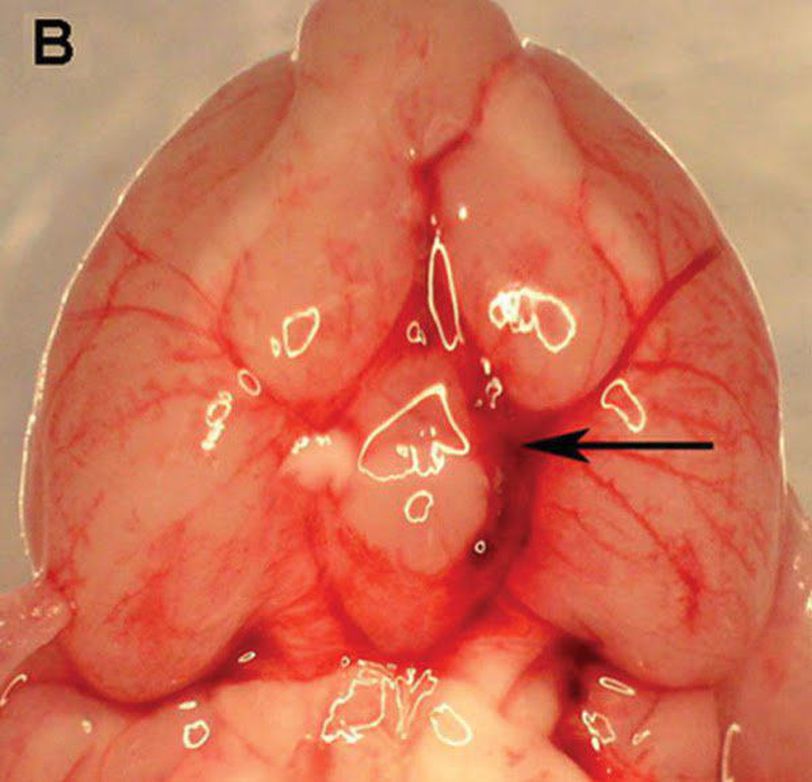

D: Cerebral vasospasm is an independent predictor of poor outcome after subarachnoid hemorrhage (SAH). The nitric oxide-cyclic GMP (NO-cGMP) vasodilatory pathway is strongly implicated in its pathophysiology. Preliminary studies suggest that phosphodiesterase 5 (PDE5) – an enzyme that degrades cGMP – may play a role, as the PDE5 inhibitor sildenafil was found to reduce vasospasm after SAH. However, several questions that are critical when considering translational studies remain unanswered. OBJECTIVE: To elucidate the mechanism of action of sildenafil against vasospasm, and to assess whether sildenafil attenuates SAH-induced neuronal cell death, improves functional outcome after SAH, or causes significant physiological side effects when administered at therapeutically relevant doses. METHODS: SAH was induced via endovascular perforation in male C57BL6 mice. Beginning two hours later, mice received sildenafil citrate (0.7, 2 or 5mg/kg P.O. BID) or vehicle. Neurological outcome was assessed daily. Vasospasm was determined on post-SAH Day 3. Brain PDE5 expression and activity, cGMP content, neuronal cell death, arterial blood pressure (BP), and intracranial pressure (ICP) were examined. RESULTS: We found that PDE5 activity (but not expression) is increased after SAH, leading to decreased cGMP levels. Sildenafil attenuates this increase in PDE5 activity and restores cGMP levels after SAH. Post-SAH initiation of sildenafil was found to reduce vasospasm, decrease neuronal cell death, and markedly improve neurological outcome, without causing significant physiological side effects. CONCLUSION: Sildenafil-an FDA-approved drug with a proven track record of safety in humans -is a promising new therapy for vasospasm and neurological deficits following SAH.